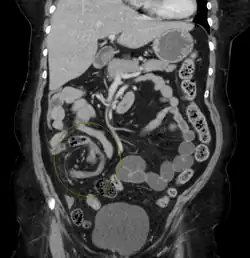

| Coronal CT of the abdomen, demonstrating a volvulus as indicated by twisting of the bowel stock | |

Coronal view of sigmoid volvulus with "whirlpool sign" -

CT scan of a small bowel volvulus. It shows two juxtaposed segments of narrowing, which is the spot of mesentery rotation. The other signs indicate strangulation. -

CT scan of a cecal volvulus